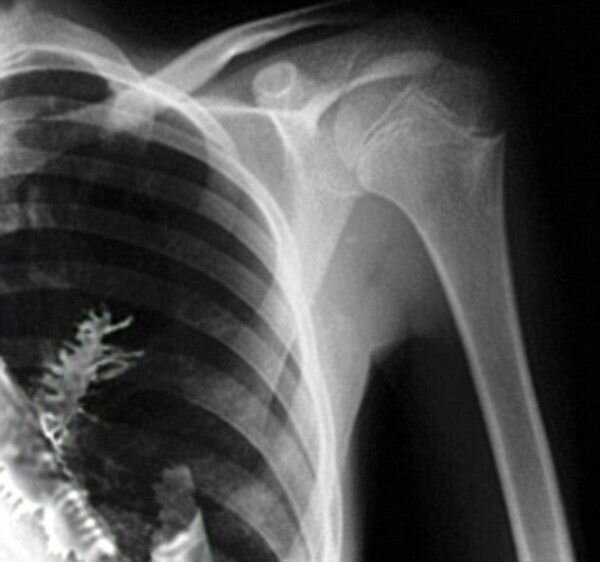

Четыре года назад в теле Артёма Сидоркина хирурги нашли настоящее дерево. Житель Ижевска несколько месяцев мучился болью в груди и кашлял кровью. Врачи поставили ему страшный диагноз и отправили парня на операцию. Даже открыл грудную клетку, доктор не сомневался, что Артём рак. Но прежде решил отдать кусочек органа на срочное исследование. Сделал надрез и наткнулся на… зелёную еловую ветку.

Елочку достали и измерили - 5 сантиметров. Врачи стали гадать, как же она туда попала? Ведь не мог же он её проглотить - она бы не прошла в лёгкое.

Выяснили, что пациент вдохнул крошечное хвойное зёрнышко, которое внутри его организма нашло подходящие условия для прорастания. Воздух и влага есть, не хватает только света, поэтому и цвет ёлки серовато-зелёный.

Кусочек лёгкого Артёма с веточкой поместили в специальный раствор для изучения. После таких историй невольно подумаешь: а стоит ли дышать полной грудью?